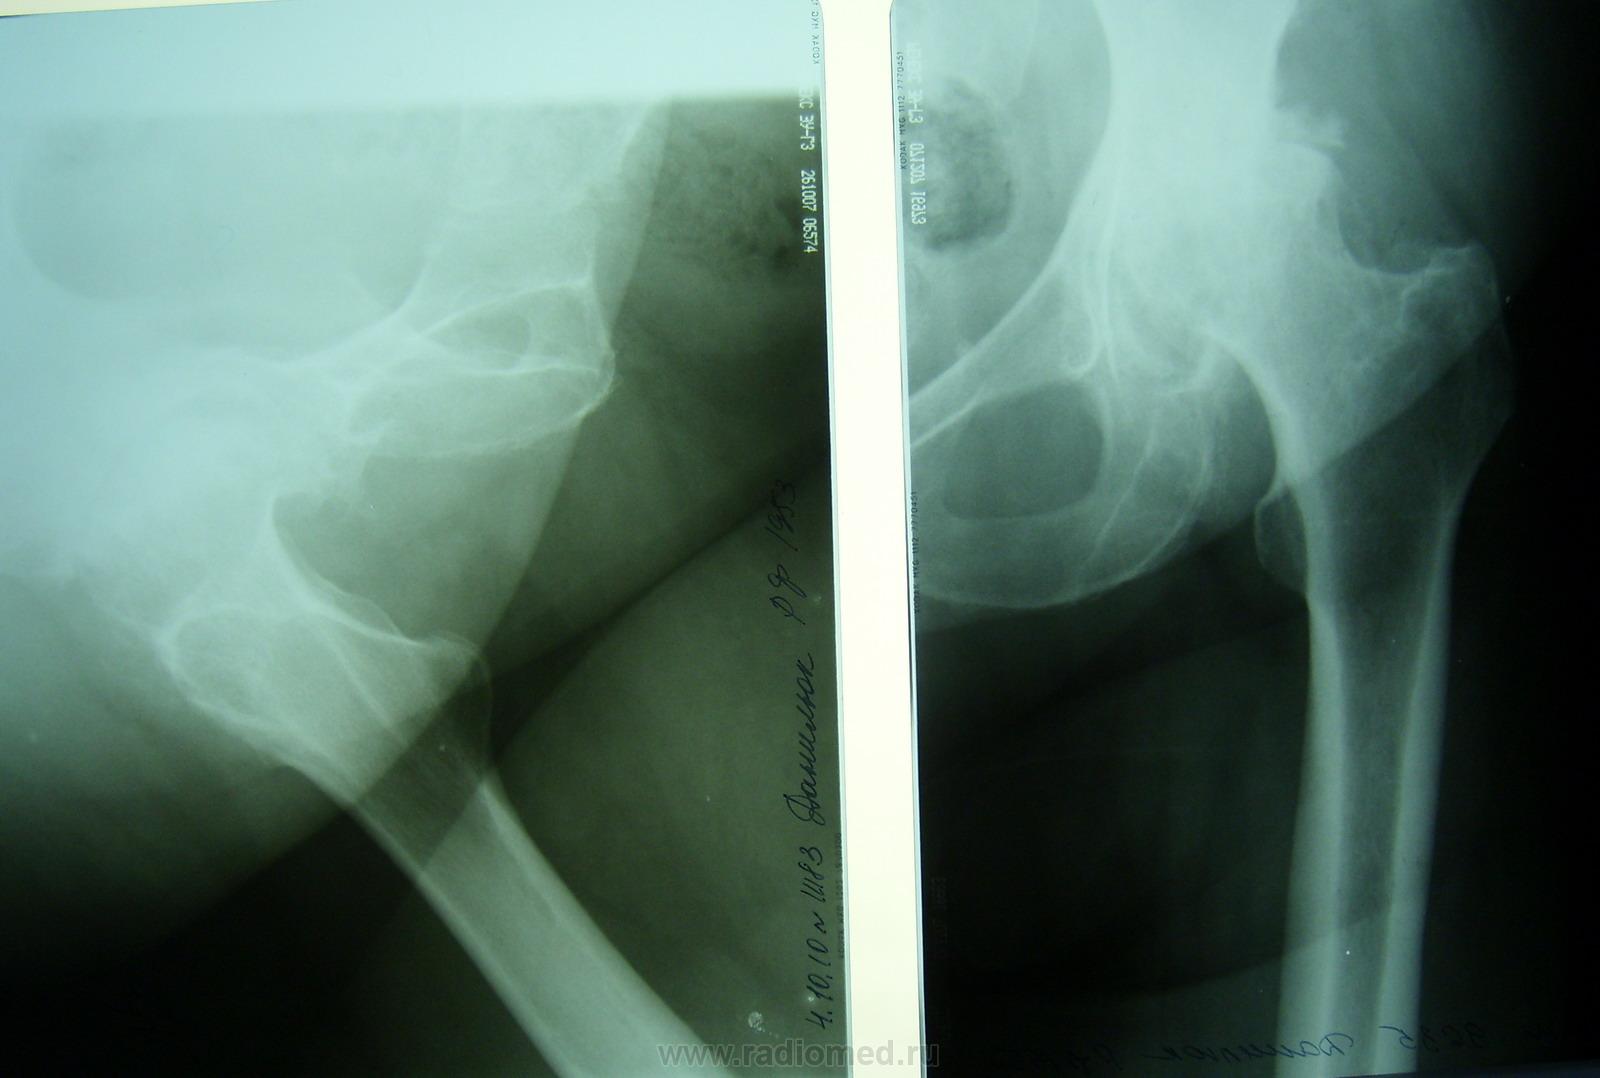

Пол пациента: Мужской пол Тип патологии: Врожденная патология Область исследования: Скелетно-мышечная система Методы исследования: Rg Пациент преклонного возраста обратился в поликлиннику с жалобами на боли в левом тазобедренном суставе. Правый сустав мне не оставили. ID:7626 Mon, 04/10/2010 - 21:09 #1 Makcimalist Offline Last seen: 11 years 10 months ago Joined: 08.05.2010 - 14:28 Posts: 1994 Глазков Игорь Артурович wrote: Пациент преклонного возраста обратился в поликлиннику с жалобами на боли в левом тазобедренном суставе... Немудрено - деф. остеоартроз 3-4 ст.. Похоже на последствия асептич. некроза головки бедра (деформирована- уплощена), кисты в ней же. -------------- "Просто, по видимости, не видеть логики в очевидных вещах - это тоже одно из свойств некоторых умов, наряду с грустными думами о свойствах ума других." © Vega 08/10/2011 Tue, 05/10/2010 - 13:49 #2 Vikkur Offline Last seen: 4 years 10 months ago Joined: 24.09.2009 - 14:34 Posts: 1749 да головка явно пострадавшая ..кисты со склеротическим ободком..и процесс похоже давний - выраженные компенсаторные остеофиты вертлужной впадины.Приложения: Виктор. Tue, 05/10/2010 - 15:46 #3 Helios Offline Last seen: 9 months 3 weeks ago Joined: 06.08.2010 - 15:16 Posts: 4417 Makcimalist wrote: Глазков Игорь Артурович wrote: Пациент преклонного возраста обратился в поликлиннику с жалобами на боли в левом тазобедренном суставе... Немудрено - деф. остеоартроз 3-4 ст.. Похоже на последствия асептич. некроза головки бедра (деформирована- уплощена), кисты в ней же. Напоминает болезнь Пертеса, вовремя не диагностированную. Wed, 06/10/2010 - 11:32 #4 DR.RAD Offline Last seen: 11 years 10 months ago Joined: 25.03.2009 - 18:22 Posts: 805 а подвывиха в суставе нет, помоему головка смещена кверху. Wed, 06/10/2010 - 11:36 #5 DR.RAD Offline Last seen: 11 years 10 months ago Joined: 25.03.2009 - 18:22 Posts: 805 пациент- мужчина в возрасте, а онко у него нет?Приложения: Wed, 06/10/2010 - 19:51 #6 Глазков Игорь А... Offline Last seen: 11 months 2 weeks ago Joined: 19.12.2008 - 20:41 Posts: 1597 получается снимки обрабатывать. Спасибо. Прийди к Себе Wed, 06/10/2010 - 19:52 #7 Глазков Игорь А... Offline Last seen: 11 months 2 weeks ago Joined: 19.12.2008 - 20:41 Posts: 1597 DR.RAD wrote: пациент- мужчина в возрасте, а онко у него нет? про онкологию в карточке ничего не сказано. Прийди к Себе

Немудрено - деф. остеоартроз 3-4 ст.. Похоже на последствия асептич. некроза головки бедра (деформирована- уплощена), кисты в ней же.

да головка явно пострадавшая ..кисты со склеротическим ободком..и процесс похоже давний - выраженные компенсаторные остеофиты вертлужной впадины.

а подвывиха в суставе нет, помоему головка смещена кверху.